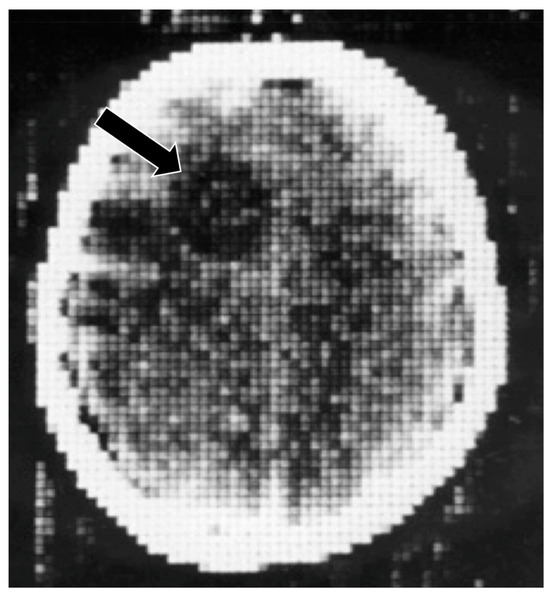

Intracranial hematomas: CT, heavily T2*-weighted gradient echo (T2*-wGE), susceptibility phase map (SPM) and partly unwrapped SPM (uSPM) 0.15 T (1987) images [12]. The CT image shows the intraparenchymal and ventricular hematomas with high signal. These images show some low signal on the T2*-wGE image. There are specific changes due to susceptibility contrast seen on the SPM and uSPM phase maps (arrows).

Figure 11.